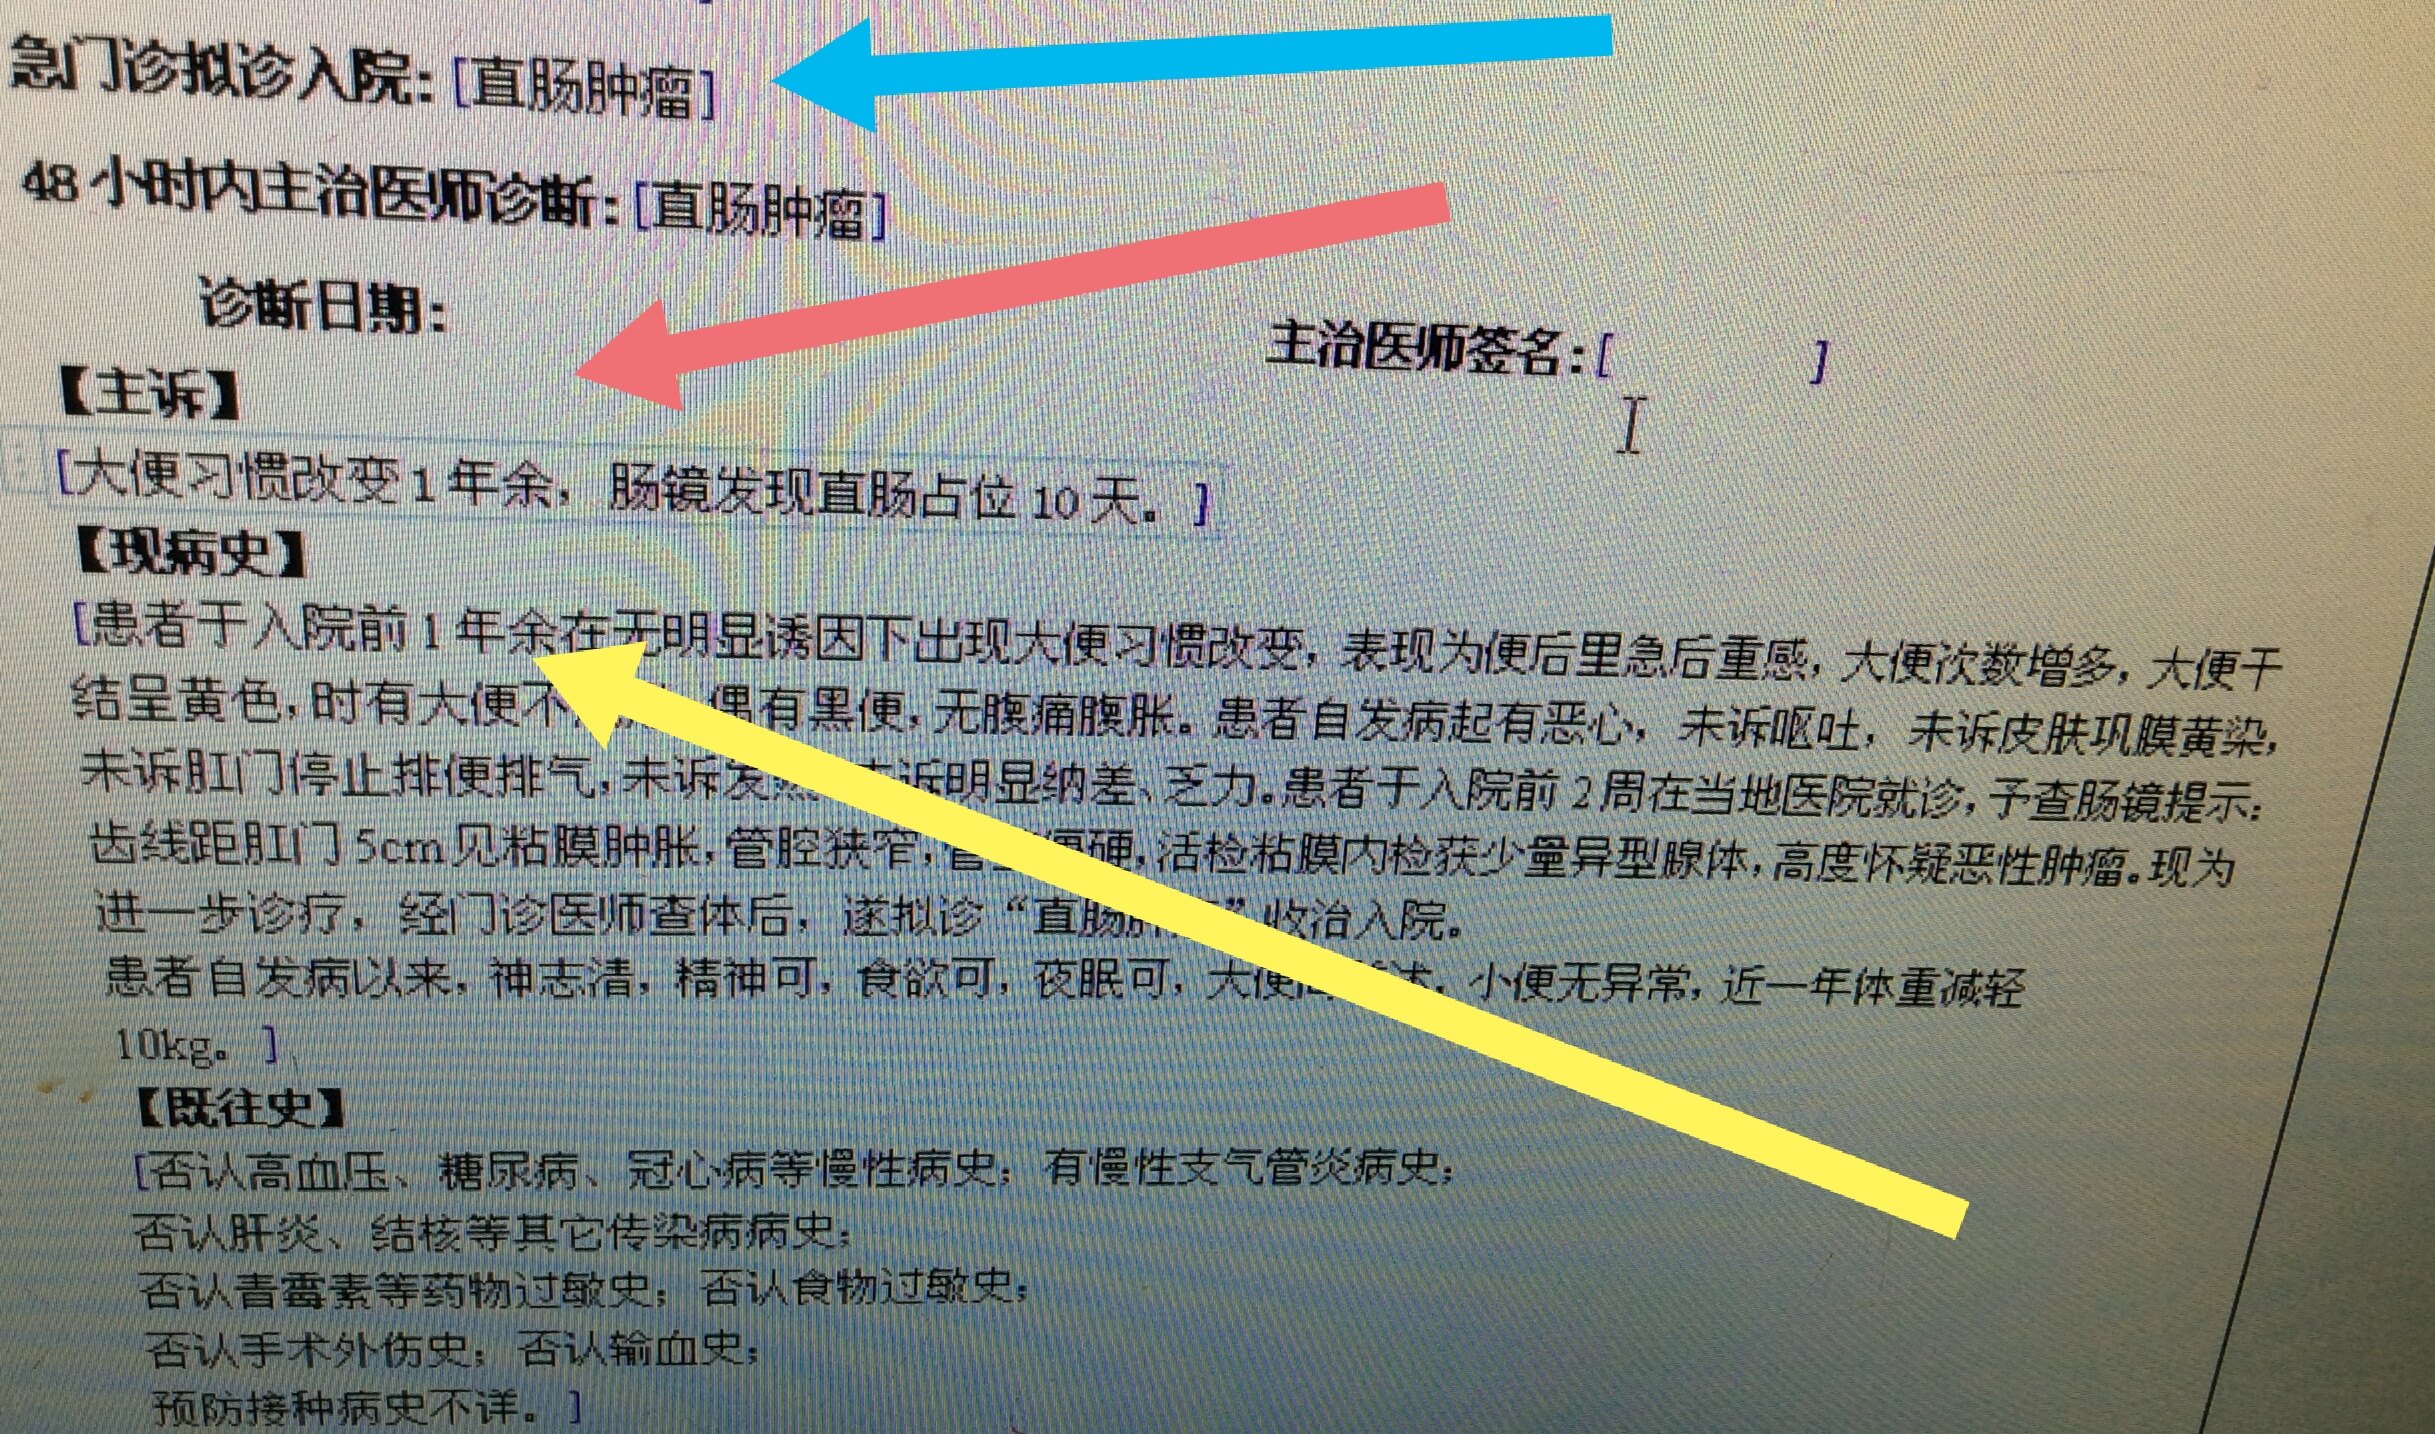

下面带了的就是这样一个特殊的前列腺癌患者。男性,75岁,一年多前无明显诱因出现大便习惯改变,次数增多,时有不成形,偶有血便。没有引起足够重视。直到最近才肠镜发现直肠肿块,外院活检提示见少量异型腺体,高度怀疑恶性肿瘤。

几天前,入我院行肠镜检查,并活检,显微镜下可见癌浸润于直肠粘膜之间。